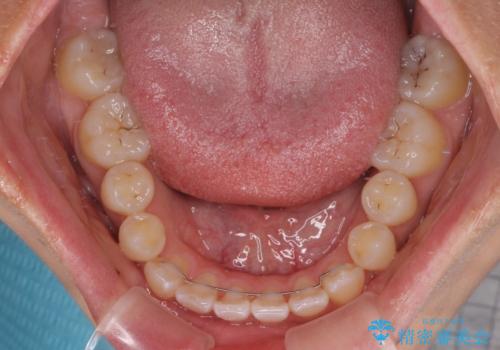

急速拡大装置で上顎骨を十分に拡大できたことで、非抜歯で八重歯を歯列に納めることができました。

患者様はもちろん、我々もここまで綺麗に仕上げられるとは想像もできず、お互いに大変満足な治療となりました。